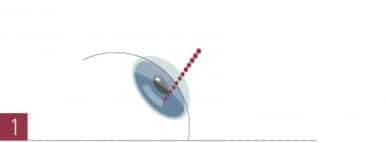

Zuerst wird ein Tunnel für das Einsetzen der Keraringe präpariert. Hierfür wird – wie bei der Femto-LASIK – ein Femtosekunden-Laser eingesetzt, der innerhalb von 6 Sekunden die Schnitte unter höchster Präzision setzt.

Zuerst wird ein Tunnel für das Einsetzen der Keraringe präpariert. Hierfür wird – wie bei der Femto-LASIK – ein Femtosekunden-Laser eingesetzt, der innerhalb von 6 Sekunden die Schnitte unter höchster Präzision setzt.